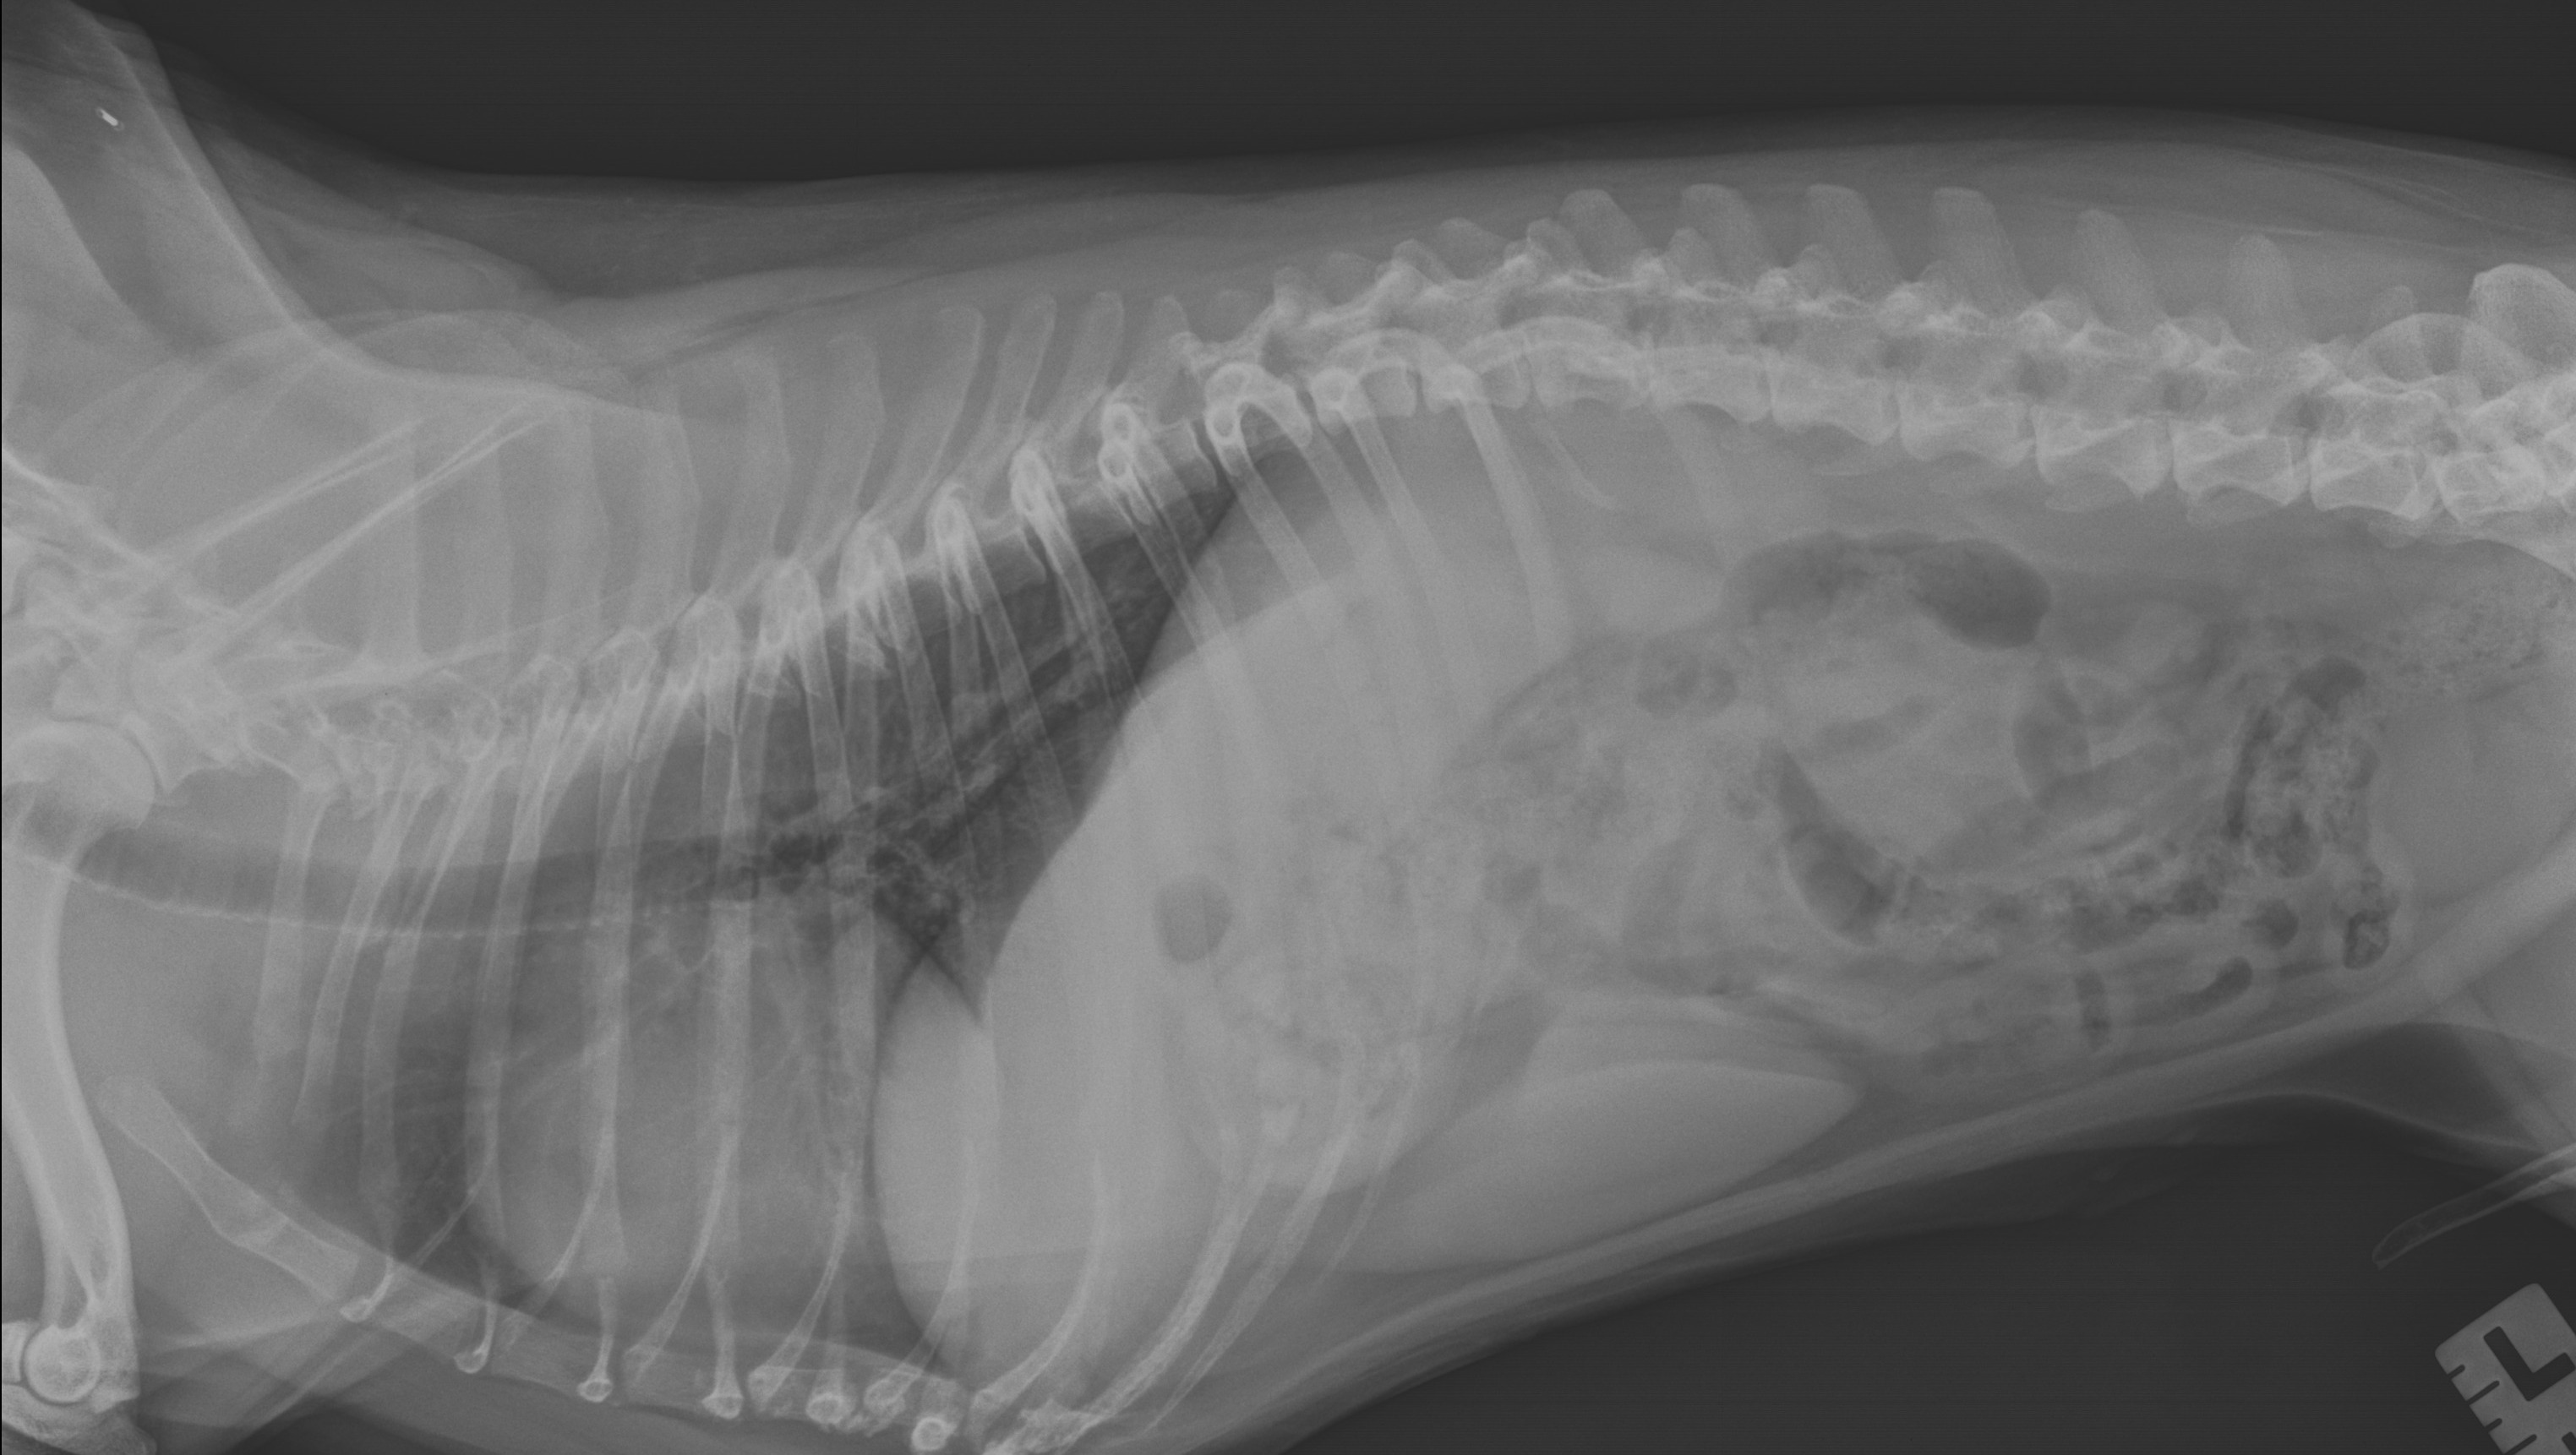

Hello my name is Cooper. I am a 7 year old chocolate Boston Terrier. Up until 2 weeks ago, I was a very energetic loving dog. I loved to play with my two Boston Terrier sisters. My mom went to let us out to potty one morning, I couldn't move off the sofa. My mom put me down on the floor, I just collapsed over. I was shaking and yelping in pain. My mom rushed me to an emergency vet clinic. For them to say everything look fine. Two days later I just got worse. So my mom took me to a different emergency vet hospital. There the vet told my mom I possibly had IVDD. Dr sent me home with a muscle relaxer and pain medication. It has been a week later. I am not getting any better. Dr told my mom that I do have IVDD. There are 5 stages of IVDD. I am near stage 3. The dr gave my mom a diagnosed plan to treat me. It is going to cost anywhere from $4000 to $8000 to get me running and playing again.

Alittle info about IVDD: Intervertebral disc disease in dogs is a medical condition that causes spinal compression and requires immediate attention. Compression of the discs within the spinal vertebrae causes severe spinal and nerve pain, and sometimes even paralysis.

An intervertebral disc is essentially the cushion between each of the bones within a dog’s spinal cord. The spine is made up of individual bones called vertebrae, and in between each vertebrae sits a disc shaped material that has a firm, fibrous covering on the outside with a gelatinous like substance on the inside of the disc. These discs help cushion and protect the bones of the spine. A dog’s spinal cord is comprised of the following bones:

There are two types of IVDD that can occur within dogs. Cooper has type 1.

Type I: This form of IVDD occurs when the intervertebral disc becomes calcified and then suddenly protrudes from within the spine, which causes very painful pressure along the spine and associated nerves. Also known as a herniated disc, often something as simple as a wrong movement can cause the calcified disc to protrude. Additionally, the disc can protrude in different directions, thus causing different types of pain. If the disc protrudes upward, it can cause bruising and compression of the spine. If it protrudes sideways, it will hit the nerves where they exit the spinal column. Either type of protrusion causes sharp pain and a reduction of nerve function.

There 5 stages Cooper is in between 2 and 3.

Stage II: Your dog will have moderate to severe pain within the neck or lower back areas.

Stage III: This stage is when a dog experiences partial paralysis, also known as paresis. This may result in difficulty walking, incoordination, or an inability to stand.